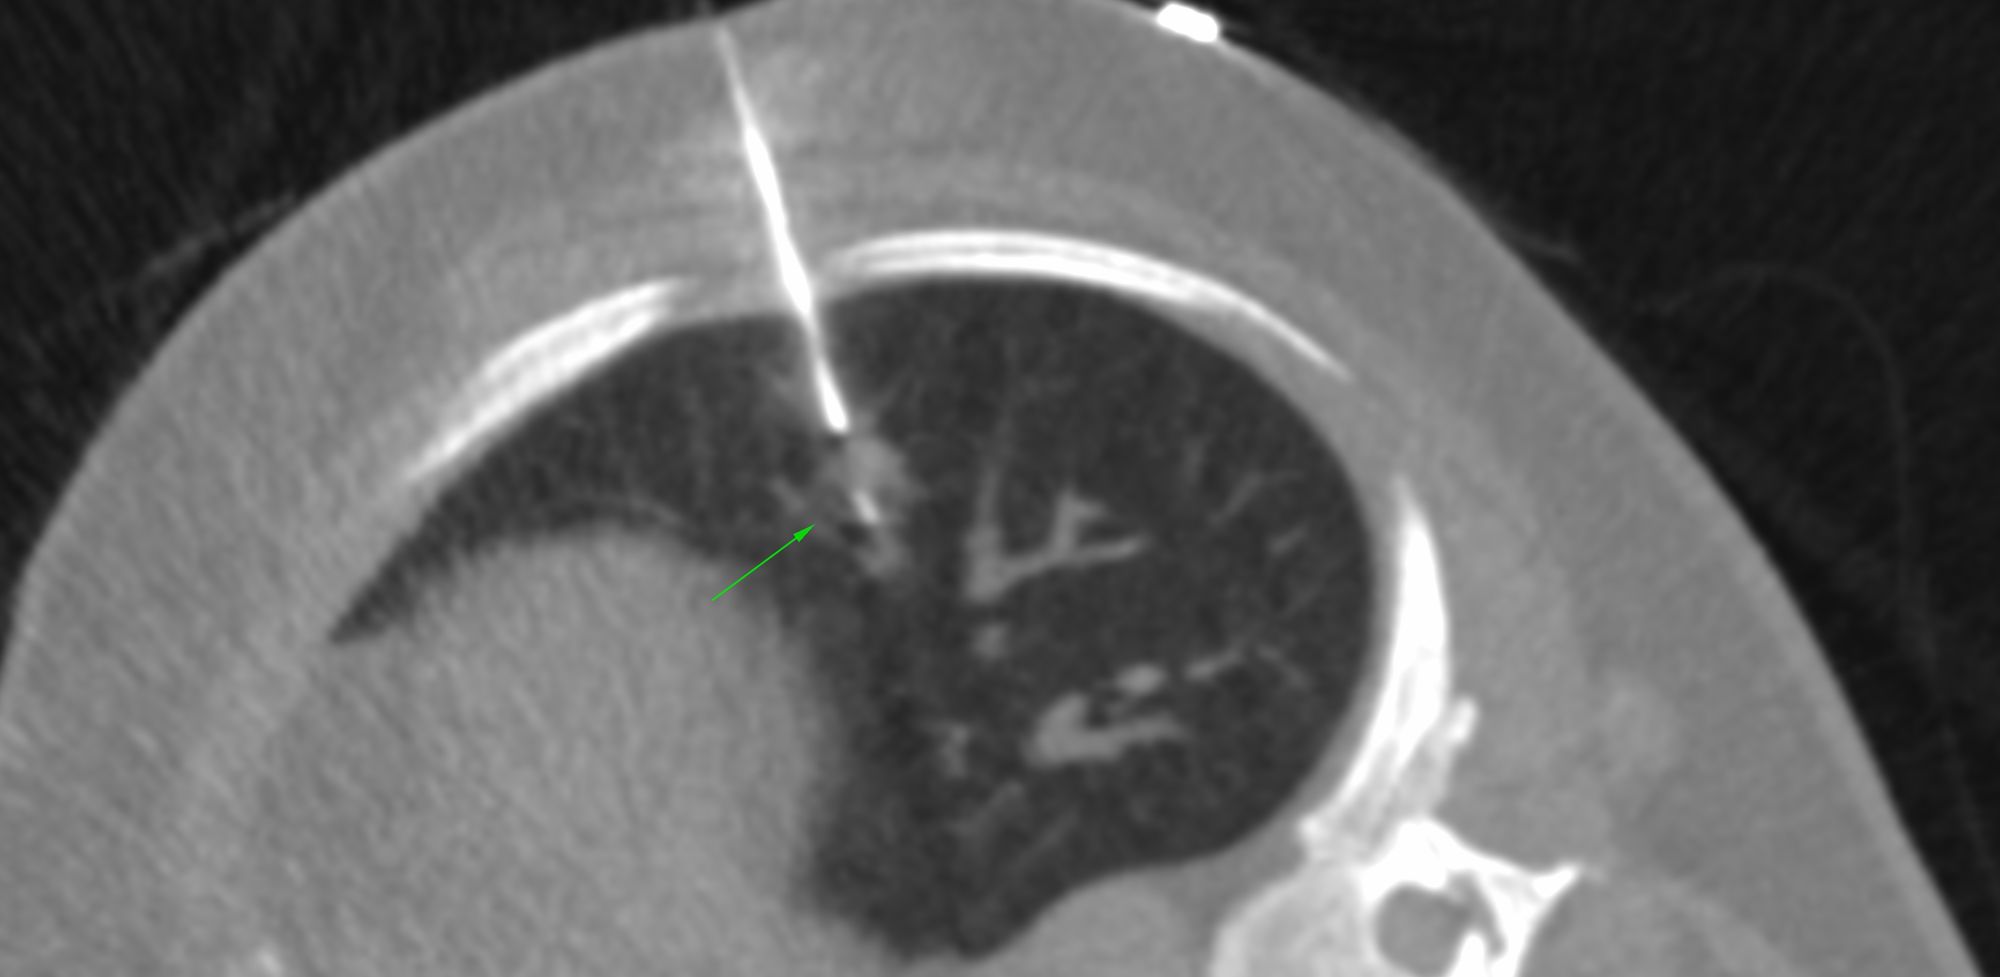

Case 8: Respect the Lung - A Tale of Two Biopsies and Complications